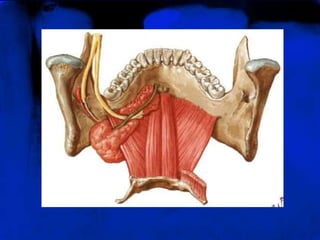

TUBERCULOS GENI ( RO)

São saliências ósseas

localizadas na porção

mediana da mandíbula, as

quais dão inserção aos

músculos milo-hióide e

genioglosso, aparecendo

nas radiografias periapicais

como um anel radiopaco

abaixo do ápice dos

incisivos centrais,

circundando a foramina

lingual

TUBERCULOS GENI (RO) São saliências ósseas localizadas na porção mediana da mandíbula, as quais dão inserção aos músculos milo-hióide e genioglosso, aparecendo nas radiografias periapicais como um anel radiopaco abaixo do ápice dos incisivos centrais, circundando a foramina lingual